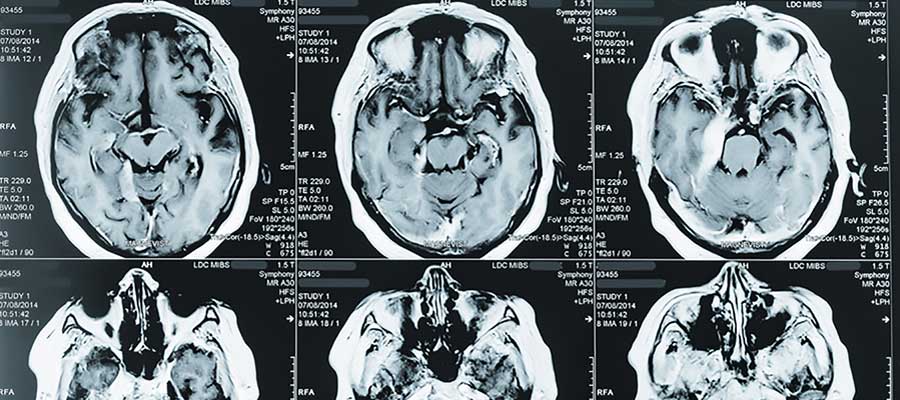

Magnetic Resonance Imaging (MRI) is actually a medical imaging process which is utilized in radiology in the formation of physiological and anatomic body processes. MRI scanners employ radio waves, magnetic field gradients and strong magnetic fields to create body organ images. That is why, a qualified MRI tech is necessary to capture the images the doctor wants.